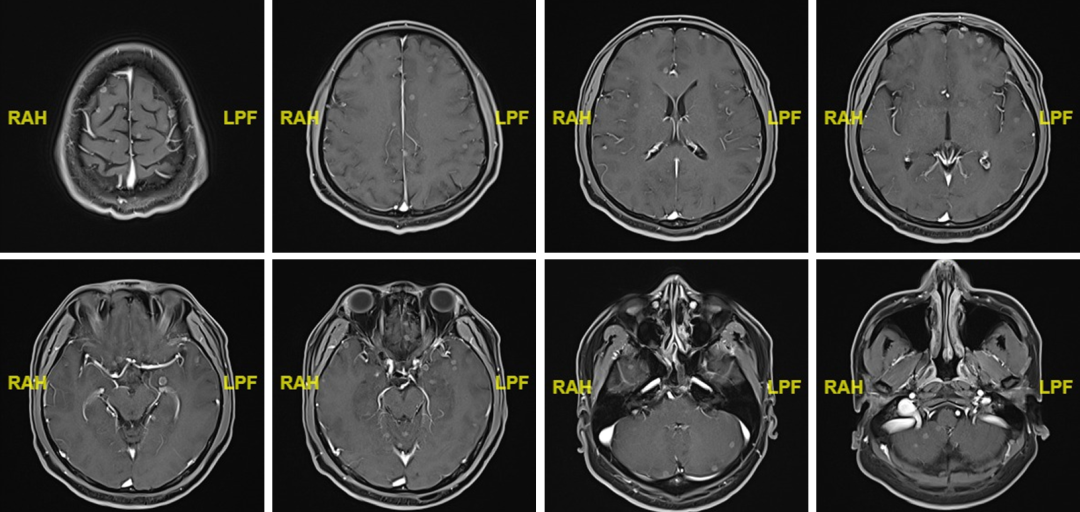

随访:2022.09.23脑MR提示大脑及小脑内多发强化结节,大者约8mm,脑内多发转移。

图6.C6后脑MR影像

后续治疗:2022.10.06起行全脑放疗,DT:30Gy/10Fx。斯鲁利单抗400mg d1 q3w维持。